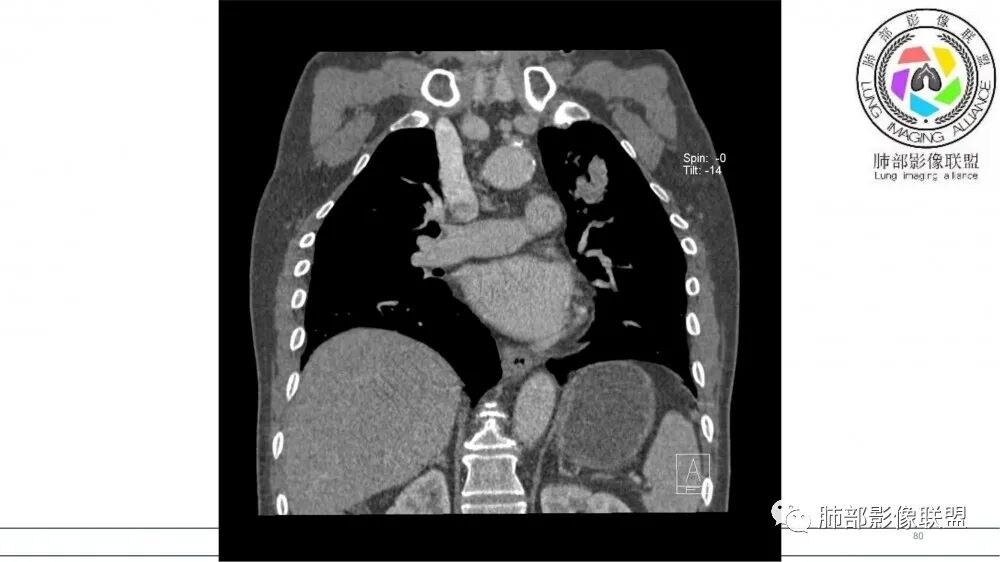

指套征,扩张支气管内软组织强化,远侧肺野阻塞性炎,纵隔、左肺门肿大淋巴结;老年男性,吸烟,考虑鳞癌,鉴别小

老年男性,术前检查肺气肿背景,左肺上叶结节,沿支气管蠕虫样生长,左肺门及纵隔淋巴结肿大,增强扫描不均匀强化,血管包绕,结合吸烟史,考虑小细胞肺癌。

2021年8月6日晨读病例结果:小细胞肺癌

指套征:是影像征象,胸部平片表现为手指状密度增高影,以肺门为中心呈放射状分布,CT显示扩张支气管内低密度黏液栓形成或实性病变,呈管状、树枝状或卵圆形密度增高影;支气管扩张伴近端梗阻时,扩张支气管内部黏液分泌物不能排出而形成。可以伴随远端空气潴留征、阻塞性炎症。

按照肿瘤发生部位,SCLC 主要有中心型与周围型。

研究报道,中心型 SCLC 经 CT 扫描后通常支气管表现为鼠尾样狭窄,肺门或纵隔肿块明显,由于肿块沿管壁生长表现为顺延支气管形态的不规则形状。病灶相对特征性影像学表现比如鸭蹼状、腊肠状、葫芦状及葡萄状改变,可以出现血管包埋,很少有空洞、空泡,较少引发肺不张,阻塞性炎症成都较轻。与一般肺癌比较,恶性程度高,侵袭力强、病灶很小就容易远处转移!Herzberg 等[19]研究指出,20%以上 SCLC 倍增时间短,预后不良。